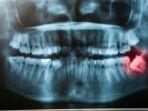

Dr. drg. Munawir H. Usman, SKG., MAP mengatakan jika dengan pemeriksaan rontgen foto gigi impaksi bisa dideteksi.